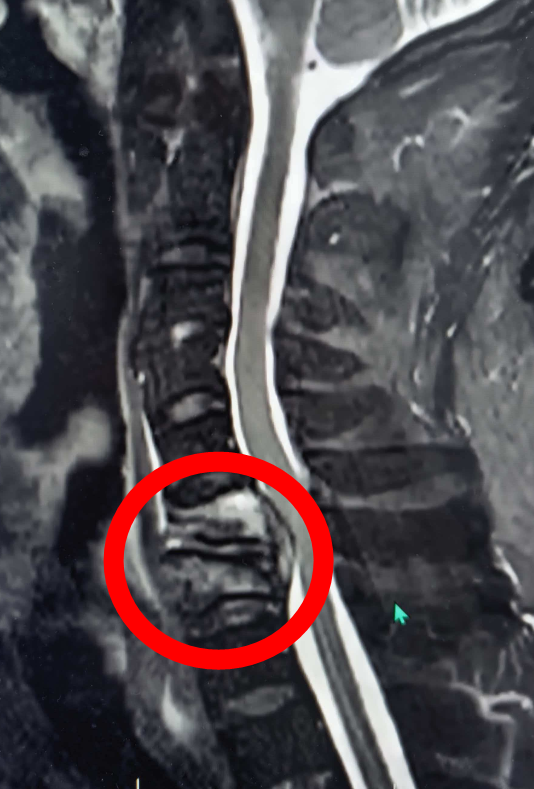

9个月前,刘先生突发颈肩部及双上肢疼痛,逐渐出现双下肢麻木、无力,行走困难,双下肢不完全瘫痪,每日备受折磨,当地医院予以相关检查显示其颈6-7椎体骨质破坏,颈椎不稳,考虑感染性病变,还伴随椎管内脓肿、脓肿压迫导致脊髓神经损伤,若不及时手术,随时可能下肢完全瘫痪。

抱着最后一线希望,刘先生来到湘南学院附属医院脊柱外科。科室团队接诊后,立刻意识到病情的复杂性:患者颈椎感染严重,双下肢已经不完全瘫痪,需手术干预,而严重的心脏问题让常规手术变成“生死挑战”。

为给患者争取生机,科室迅速启动全院多学科会诊,联合心血管内科、麻醉科、呼吸科、临床药学、重症医学科等专家反复评估。心内科专家指导术前心功能优化,麻醉科专家制定术中循环监测与应急方案,脊柱外科团队则选择创伤更小、恢复更快的颈椎前路手术方式,直接清除颈椎前方的病灶,重建脊柱稳定性,最大限度降低对心脏的负荷。

2025年12月17日,在全身麻醉下,脊柱外科主任王炯团队凭借精湛技术,顺利完成颈椎前路融合术+病灶清除+椎管减压+内固定术,全程避开神经与血管,仅用1.5小时完成手术,术中出血量50ml,远超预期。术后患者转入重症监护室,在多学科团队协同治疗下,病情稳定好转。